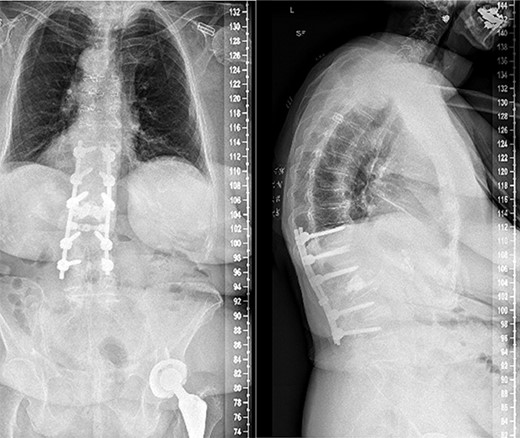

Anterior–posterior and lateral radiographs of the patient’s spine postoperatively, following L1-L2 laminectomy and T11-L4 posterior fusion.

Segmental spinal instrumentation was placed at L4, L3, L1, T12, and T11 with appropriate positioning of the screws confirmed with biplanar fluoroscopy. Laminectomy was also performed at L2 and L1 with adequate decompression of the neural elements. The fracture was thereafter reduced using gentle cantilever maneuvers. One crosslink was placed, and a final fluoroscopic image confirmed the appropriate positioning of implants and reduction of the fracture and deformity. The wound was copiously irrigated, and the posterolateral spine was decorticated and packed with local autograft as well as demineralized bone matrix. Plastic surgery ensured proper closure using muscle flap reconstruction of the patient’s posterior spine wound. Follow-ups at 2, 4, and 7 weeks later all revealed that the patient no longer had stabbing or throbbing pain, gradual improvement of the back pain down to a 3/10 in severity, well-tolerated ambulation with a walker and assist, normal CNII-VII, 5/5 strength bilaterally upper and lower extremities, and mild back soreness. Postoperative follow-up at 2 years still revealed no complications associated with the procedure with the patient having minimal back pain and soreness, supported by lateral and axial radiographs (Fig. 3).